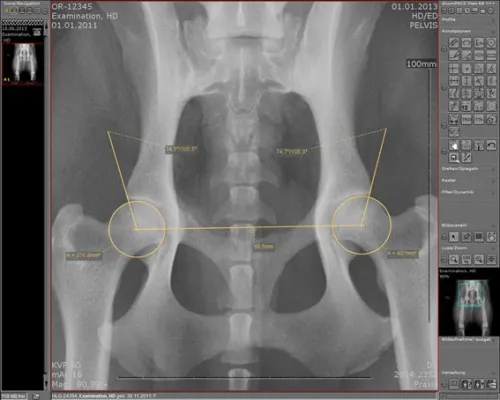

„Die intuitive Bedienung über den Touchscreen-Monitor überzeugte uns von Anfang an. Hierüber können wir die gesamte Röntgenanlage steuern“, erläutert Dr. Karl Scherer die Beweggründe für die Umstellung auf das Medici-System. „Die Toolbar ist sehr übersichtlich gestaltet und mühelos zu bedienen. Der einfache Versand von Röntgenbildern per Email an Kollegen war ein weiteres Kriterium für uns.“ Unmittelbar nach der Aufnahme sind die digitalen Röntgenbilder an allen fünf Betrachtungsstationen innerhalb der Tierklinik verfügbar. Die Bilder werden mit Hilfe des Bildmanagementsystem dicomPACS®vet archiviert.

„Die Bildqualität ist konstant gut und ich habe die Bilder jederzeit zur Verfügung“, berichtet Dr. Karl Scherer. „Wir können nun deutlich mehr als früher röntgen, denn die digitale Röntgentechnologie hat die Arbeitsabläufe in unserer Klinik außerordentlich vereinfacht. So ist das HD-Röntgen innerhalb weniger Minuten abgeschlossen – ein enormer Zeitgewinn für uns. „Dank der integrierten Werkzeuge zur Bildoptimierung ist es kein Problem, wenn durch unruhige Tiere Aufnahmen einmal nicht optimal belichtet sind. Dann korrigiere ich die Bilder einfach“, fügt Dr. Alexander Pack hinzu. „Der Einstieg ins digitale Röntgen war für uns ein Gewinn. Wichtig ist auch, dass wir jetzt schon sagen können, dass sich die Anlage binnen kurzer Zeit amortisiert haben wird“, bilanziert Dr. Karl Scherer.